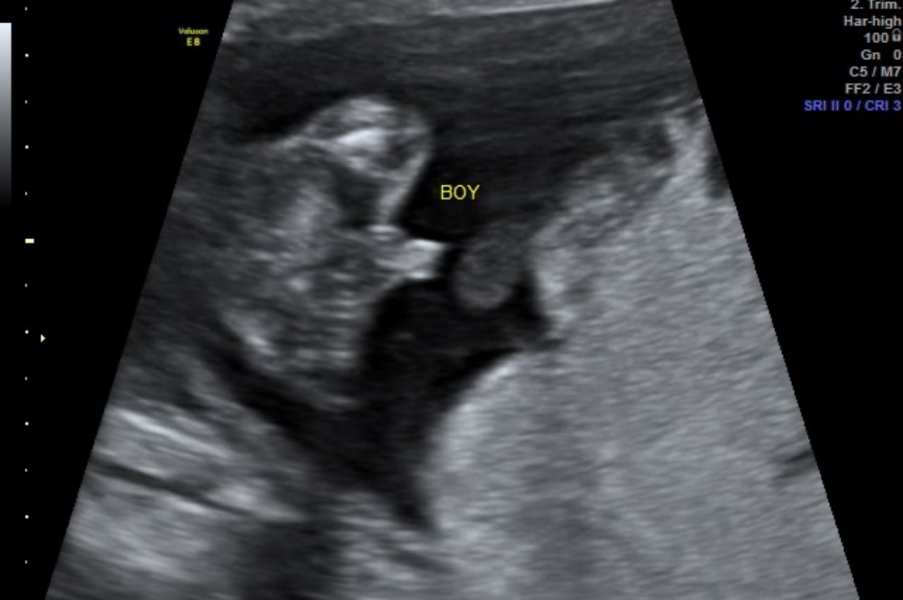

we went for a gender scan last week at 17 +3 and were told boy, but I have seen a lot of threads online about boys being mistaken before 18wks for their cord or swelling. What are people’s thoughts please, is baby definitely a boy?

Definitely boy

It's much less common for them to mistake girl for boy rather than vice versa.

I would say that definitely looks boyish and also bear in mind they are looking at a moving image with a trained eye, not just a blurry still photograph.